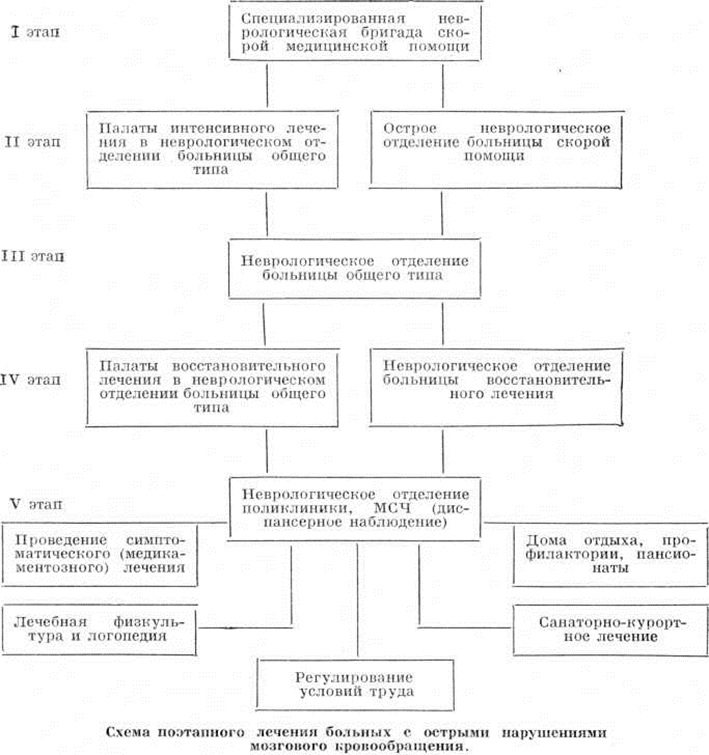

Лечебные мероприятия необходимо проводить безотлагательно, дифференцированно, в зависимости от состояния больного и характера патологический процесса в головном мозге. Ниже приводится схема поэтапного лечения больных с острыми нарушениями мозгового кровообращения.

Ранняя госпитализация больных с Инсульт должна производиться в специализированные неврологический отделения или в стационары, где имеются палаты или отделения интенсивной терапии и реанимации.

Перевозке в стационар из дома не подлежат больные в глубоком коматозном состоянии с грубым нарушением витальных функций. В тех городах, где созданы специализированные «инсультные» бригады во главе с врачом-невропатологом, оснащённые необходимой диагностической аппаратурой и средствами неотложной терапии, показания к госпитализации расширяются.